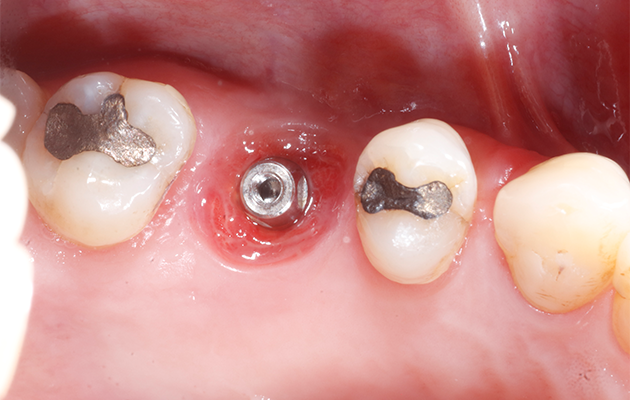

Na avaliação clínica, verificou-se o extravasamento de pus via sulco gengival no dente 16. A paciente relatava dor à palpação local e durante a percussão. Além disso, o dente 16 apresentava mobilidade grau 1, fratura de cúspides, uma extensa restauração de amálgama, lesões cariosas próximas à restauração e acúmulo de biofilme. O exame tomográfico revelou uma lesão envolvendo a raiz mesiovestibular do dente 16, com provável comunicação endoperiodontal.

1 | Aspecto inicial do dente 16. Destaque para a supuração drenada via sulco gengival